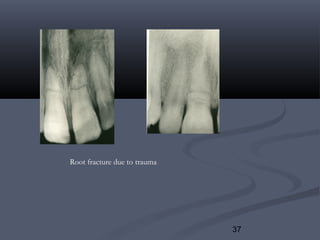

b. Root Fracture:b. Root Fracture: caused bycaused by

1.1. Excessive widening in root canals.Excessive widening in root canals.

2.2. Force seating of improper fitting post and core.Force seating of improper fitting post and core.

3.3. Caries.Caries.

4.4. Trauma.Trauma.

These have poor prognosis and should be extracted.These have poor prognosis and should be extracted.

Root fracture due to trauma